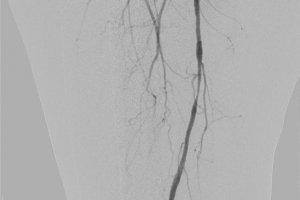

Одной из успешно выполненных эндоваскулярных операций была баллонная ангиопластика рестеноза (повторного сужения) бедренной артерии. Пациенту уже выполнялась подобная процедура полгода назад по месту жительства в связи с болью в мышцах нижних конечностей при ходьбе на расстоянии 100–200 метров. После первой операции боль прошла, однако она возобновились вновь через 7 месяцев. Осмотр и исследования позволили выявить критический рестеноз оперированной артерии.

Нашими хирургами выполнена уникальная операция на «заросшей» артерии с помощью баллонного катетера с лекарственным покрытием, показавшим свою эффективность в значительном удлинении сроков повторного стеноза артерии.

Следует отметить, что благодаря своевременно выявленной проблеме, вся операция проводилась через один прокол в паховой области, без разрезов, без наркоза (с применением местной анестезии) и длительностью всего 50 минут. Уже на следующий день пациент вновь мог свободно ходить без боли в ноге длинные дистанции.